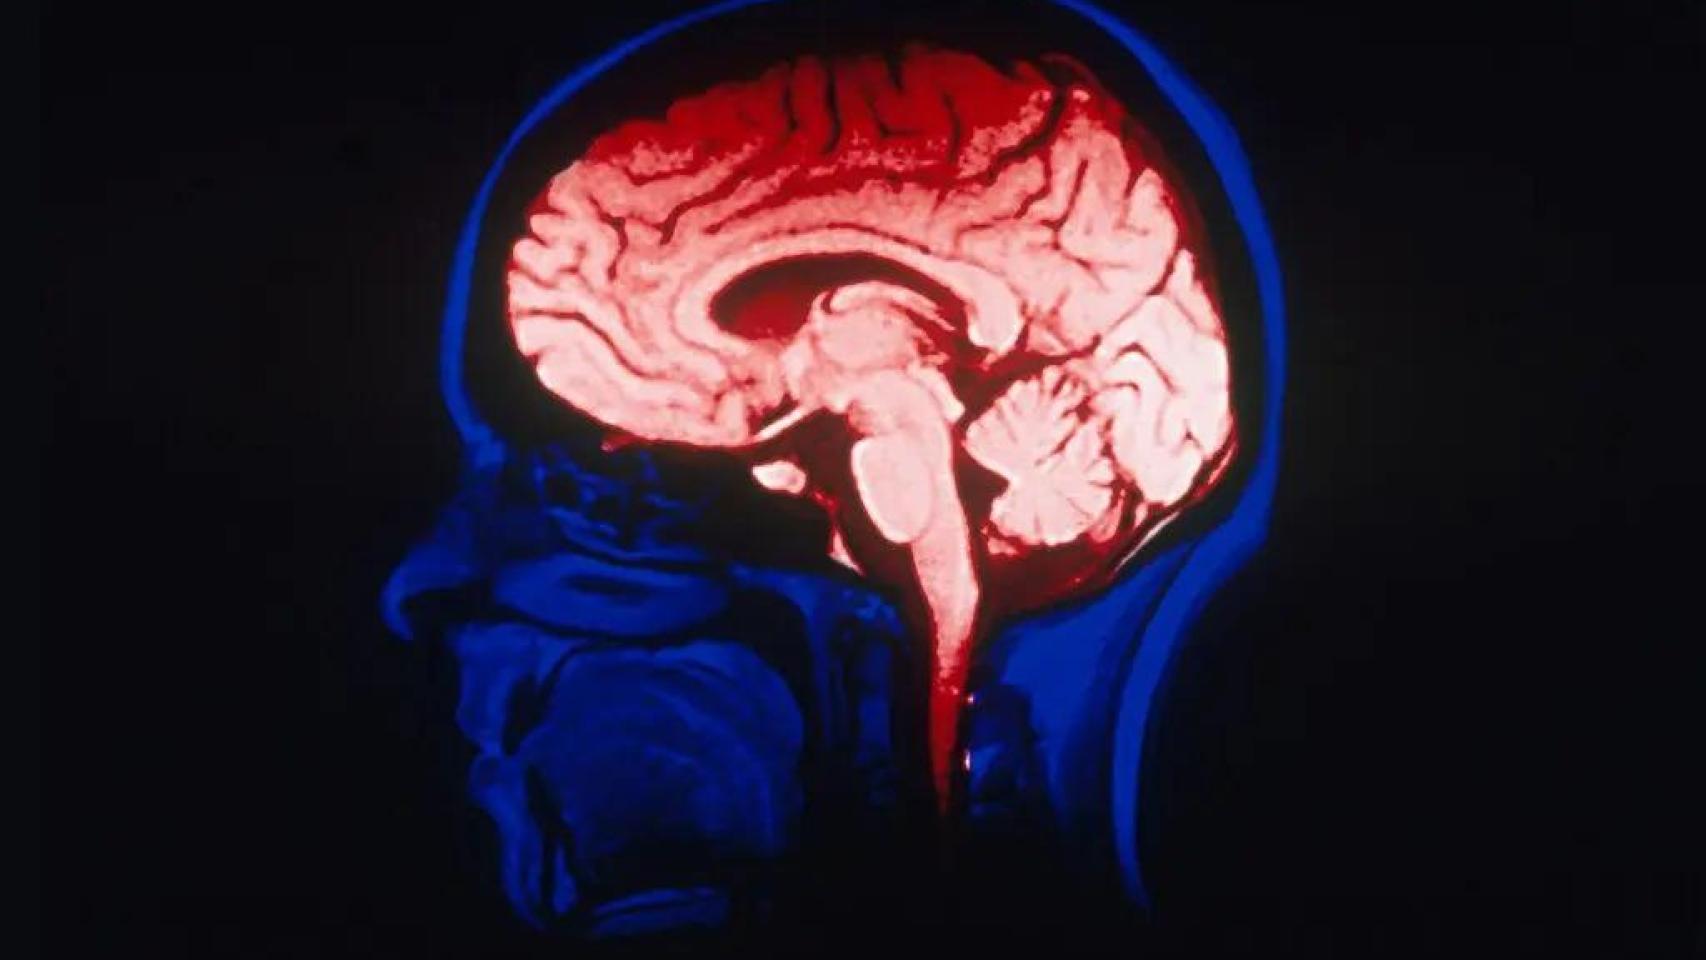

La última gran conquista de esa carrera se ha publicado esta miércoles en la revista Nature. Se trata del primer mapa completo del cerebro humano en formación, elaborado por un consorcio internacional en el que han participado más de 500 laboratorios de todo el mundo, incluidos científicos del Instituto Cajal en Madrid.

El trabajo ofrece un retrato celular y molecular del desarrollo cerebral desde las primeras semanas de gestación hasta la adolescencia. Es, en palabras de sus autores, "una guía biológica para entender cómo se construye una mente".

Así, el nuevo atlas describe con una precisión inédita cómo las células madre dan lugar a los distintos tipos neuronales, cómo se organizan las capas de la corteza y cómo se establecen los circuitos que luego sostendrán el lenguaje, la memoria o la empatía.

Los investigadores han identificado más de 3.000 tipos celulares distintos, con patrones de expresión genética que cambian a lo largo del desarrollo.